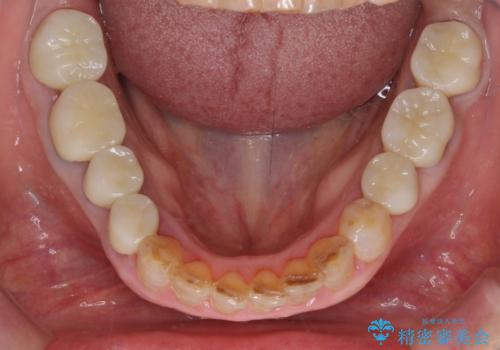

途中体調を崩されてしまい、その間に仮歯が外れてしまうなど、治療期間が長引いてしまいました。

治療期間はかかってしまいましたが、念願のメタルフリーとなり、患者様には大変満足していただきました。